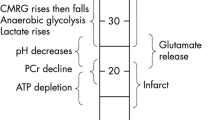

The dual-peak reductions (< 50%) in the EDC ratio currently observed, along with the previous finding on the biphasic disruption-phenomenon of BBB post-reperfusion, indicate the biphasic development of cellular edema post-reperfusion. We postulate that the EDC range, < 50%, with the time factor < 1.5 h, reflects an increased risk of cell death (i.e., the presence of a risk on the tissue destiny), and the EDC range, < 50%, with the time factor > 1.5 h, reflects the histological transformation to cerebral infarction (i.e., the early sign of tissue necrosis). As the alterations in the ADC are reportedly delayed or not significant in the paradigm of the acute permanent focal ischemia, the time factor, > 1.5 h post-reperfusion, or even > 1.5 h post-ischemia without the consideration of (or the information on) reperfusion, is essential in making an EDC-based precise (errorless) diagnosis on the tissue integrity (Fig. 5).